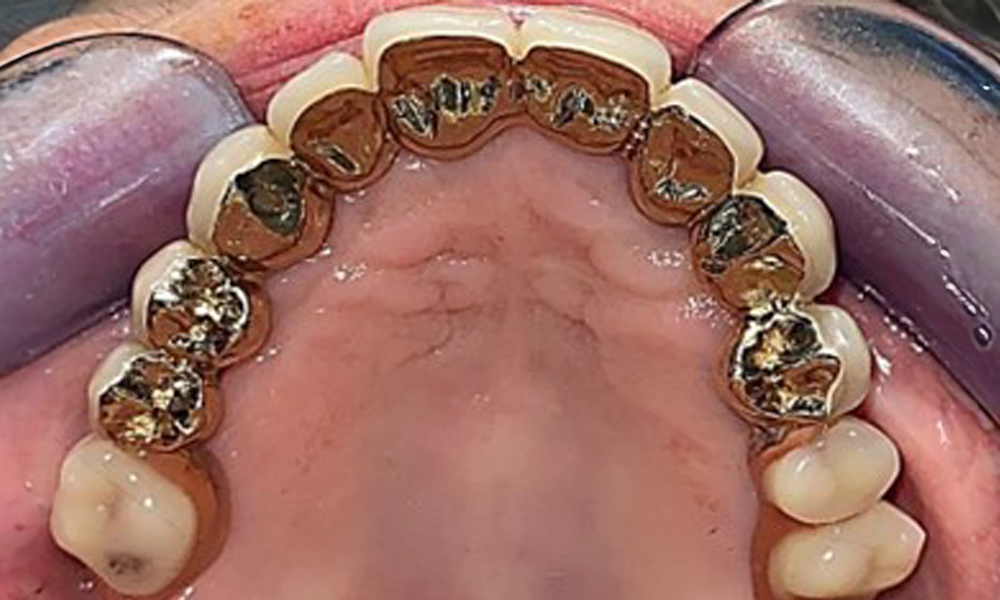

The intraoral mucosa must be examined for possible fungal infections and pressure spots. The dentures must be visually inspected for cleanliness. The present case presented with interdental discolouration, attributed to tea consumption (Fig. 7). The dentures should be professionally cleaned in the dental practice using disinfection and cleaning baths.

Basal view of the dentures for assessing cleanliness.

Fig. 7: Basal view of the dentures for assessing cleanliness.

It is also important to clean the dentures professionally in an ultrasonic bath at the dental practice, and to use disinfectant solutions to combat fungal infections if required. This also allows discolourations to be removed and gives the patient the sensation of cleanliness.